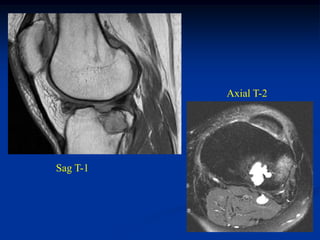

Case #124

11 year male

chondromyxoid fibroma

proximal tibia

Case # 124.1                    AP and lat x-ray

50 year male with chondromyxoid fibroma proximal

tibia with 6 months of a tender tumor mass anterior tibia

Coronal T-1 MRI

Coronal PD FS MRI

Axial PD FS MRI

Axial Gad MRI